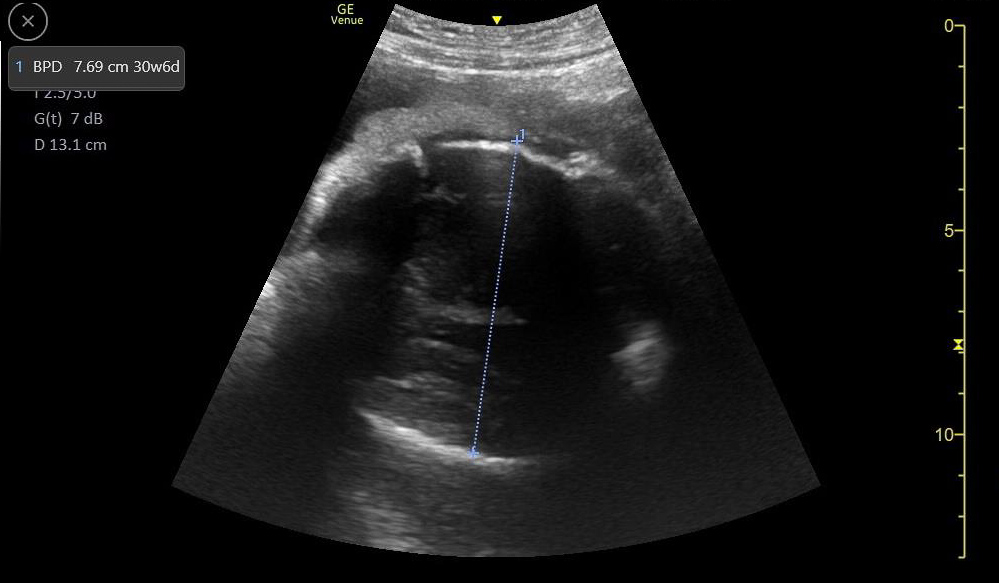

- Mechanical Risk Factors for Delivery

Figure 29. Transverse suprapubic view revealing the fetal cranium in the pelvis, consistent with a vertex presentation. Note the calipers measuring a bi-parietal diameter at 30 weeks and 6 days.